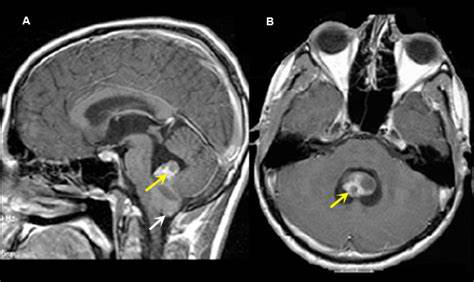

从严肃医学的角度来说,这没有可比性。影响疾病的治疗难度的因素太多了,肿瘤级别、位置、患者本人的身体状况、年纪等。室管膜瘤患者的医疗管理包括辅助治疗(即常规放疗、放疗、化疗)、瘤周水肿的类固醇治疗、幕上室管膜瘤患者的抗惊厥药物。

肿瘤切除范围是与非恶性室管膜瘤患者长期生存相关的较重要的预后因素,无论其位置如何。因此,总的全切除(GTR)是更佳的。